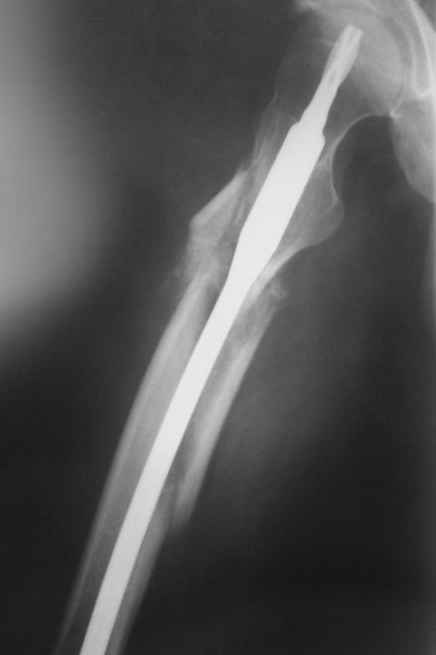

по поводу бедра - все сделано правильно, есть прекрасная апозиция основных фрагментов почти на всем диаметре перелома, в этом районе прекрасное кровоснабжение и нет никакого смысла гончяться за осколком

небольшое замечание по поводу бедра - сразу не рассмотрел - гвоздь обязательно надо было заблокировать дистально и крайне желательно -и проксимально тоже. Без блокирования не исключена ( хоть и не очень вероятна) ротация фрагментов.

Практически единственное, что делает необходимым разрез для манипуляций с промежуточным отломком бедренной кости - это его "застегивание" в илиотибиальном тракте по типу пуговицы в петле.

Отломок, расположенный так, как на показанных рентгенограммах бедра, обычно на снимках в 1-2 мес. уже располагается ближе к диафизу и

включается в мозоль.

На операции я оставил осколок в области приводящих мышц бедра (ни пальпаторно, ни спицей сдвинуть не смог, "заклинило" насмерть). Фото спустя 2 месяца после операции (PFN).